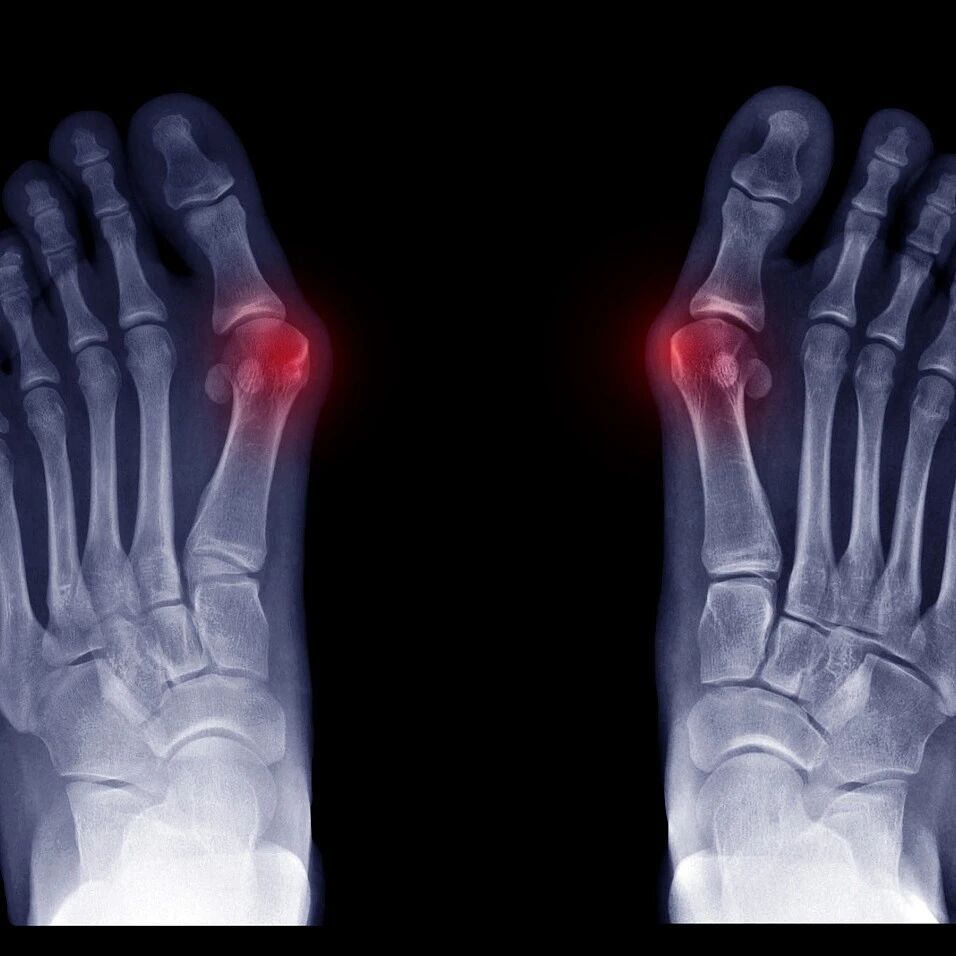

【科普先锋】告别三十年“足”忧!同仁骨科引入Spear Plate微创技术,助力拇外翻患者重塑步履

这里是上海市同仁医院的上观号。上海交通大学医学院附属同仁医院始建于1866年,是上海西区一所集医疗、教学、科研、预防、康复于一体的公立综合性医院。核定床位1200张,拥有27个临床科室和9个医技科室。医院连续九次蝉联上海市文明单位,并荣获第五届“全国文明单位”称号。